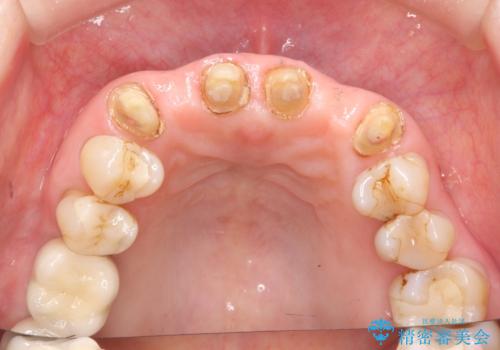

不自然な前歯ブリッジ ジルコニアブリッジによるやり替え

- 20年前に入れたブリッジの見た目の改善を求めて来院されました。

丁寧に現在装着されているブリッジを除去後、精度の高いジルコニアブリッジで審美性の改善を計画します。

前歯に限らず拡大鏡を用いた精密な形成・シリコンを用いた精度の高い印象を徹底することで治療全体の質を高め、審美性だけでなく長期的な予後を期待することができます。